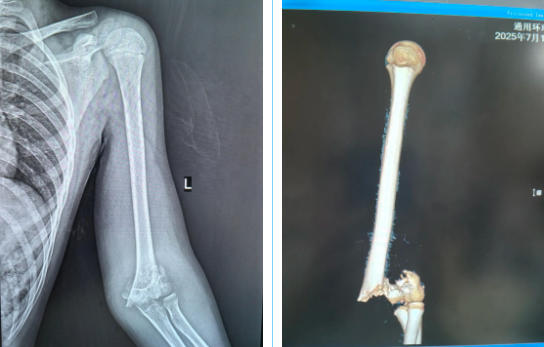

术前影像

17日7时许,小方被收住入院。彼时,距离摔伤已过去12个小时,左肘部肿胀畸形,左前臂旋转活动功能受限,左手感觉麻木,左桡动脉搏动减弱,诊断为左肱骨远端粉碎性骨折、左正中神经挫伤。“患者左手麻木,这是神经损伤的典型症状,一是要治疗骨折,二是要探查受损神经。”姬传磊主任团队明确病情后,拟行“左肱骨骨折复位复位内固定术+神经探查术”。